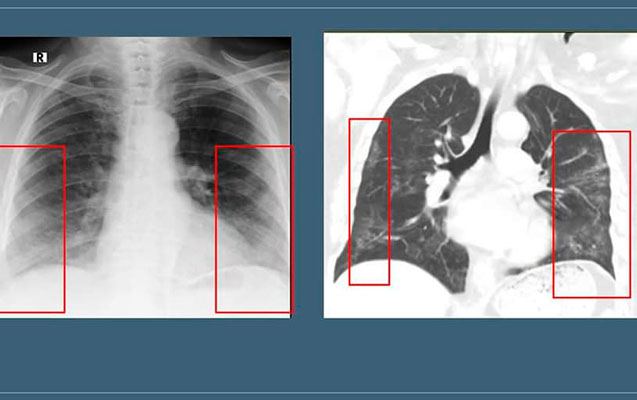

Hazırda “buzlu şüşə” görüntüsü koronavirus pnevmoniyasının əsas radiodiaqnostik əlaməti hesab edilir. Bu ,o deməkdir ki, normalda şəffaf havalı görünən ağciyərdə belə hallarda yarımşəffaf zonalar izlənilir, ağciyər sanki dumanlı görünür:

Qeyd edək ki, “buzlu şüşə” görüntüsü döş qəfəsinin rentgenoqrafiya və KT müayinələrində aşkar edilir. Lakin bu məsələdə rentgenoqrafiya müayinəsinin həssaslığı aşağıdır. Ona görə də yoluxmanın ilk 1-4 günlərində rentgenoqram 25% hallarda tam normal ola bilər. Bu, pnevmoniyanın olmaması demək deyil. “Buzlu şüşə”nin KT müayinəsində görülməsi daha spesifikdir (Şəkildə eyni xəstənin rentgenoqrafiya və KT müayinələrində buzlu şüşə görüntüsünün təsviri verilib).